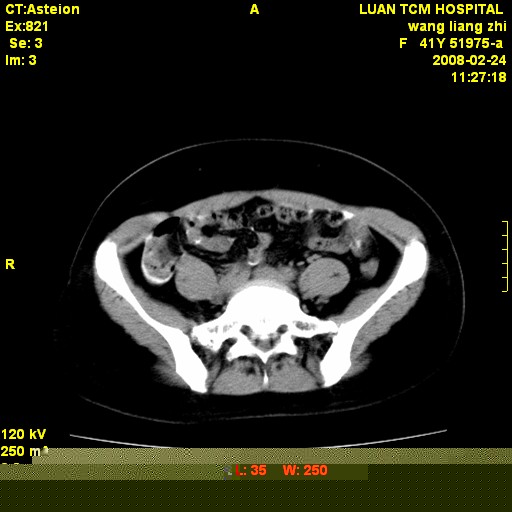

以下是引用dyqct在2009-8-23 16:17:00的发言:[br]考虑:1、造影剂进入腹腔、结肠旁沟、肝周;[br] 2、子宫明显增大(腺肌增生症?);[br] 3、膀胱显影是由于造影剂吸收后经肾分泌进入膀胱的;[br] 4、建议mri检查子宫。